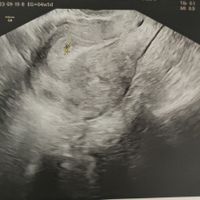

Hola! Me he animado a abrir el post y espero que poco a poco seamos muchas 🤰🏼. Yo vi mi positivo el pasado sábado y mi FPP es el 11 de Mayo. Todavía estoy de muy poquito y al ser primeriza total me...